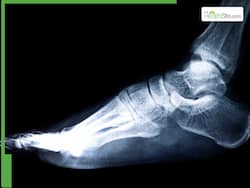

Recurring ankle sprains? Doctors explain how they can lead to chronic ankle instability and joint damage

Recurring ankle sprains may be more serious than you think. Doctor explains how repeated injuries can cause chronic ankle instability, ligament damage, long-term pain, and mobility problems.